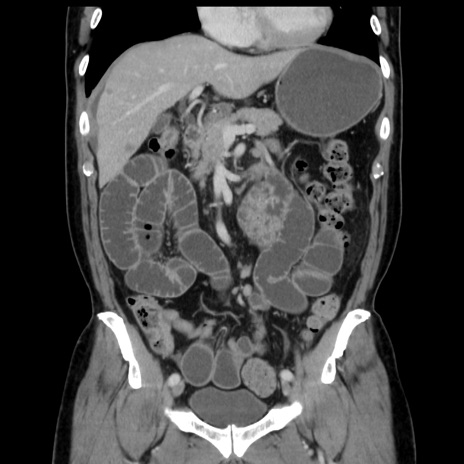

症例16(冠状断像)

【症例】 70歳代男性

【主訴】 腹痛、嘔吐

【現病歴】 約1ヶ月前より間欠的に腹痛と嘔吐あり、当院消化器内科を受診したところCTで多発する肝臓のLDAを指摘され、精査中であった。以降は消化器症状は安定していたが、2日前より嘔気と腹痛があり、同日より排便・排ガスが消失した。改善認めず、 本日、救急外来を受診した。

【既往歴】 大腸ポリープ切除後。

【身体所見】意識清明・会話良好、BT 36.3℃、BP 127/80mmHg、 P 80bpm、腹部:膨満あり、平坦・軟、上腹部正中および下腹部正中に圧痛あり、反跳痛なし、筋性防御なし。

【データ】WBC 7200、CRP 0.77